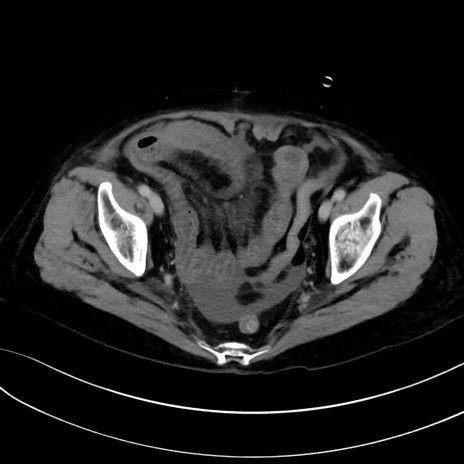

症例13 CT(横断像)1日半後

(冠状断像)1日半後